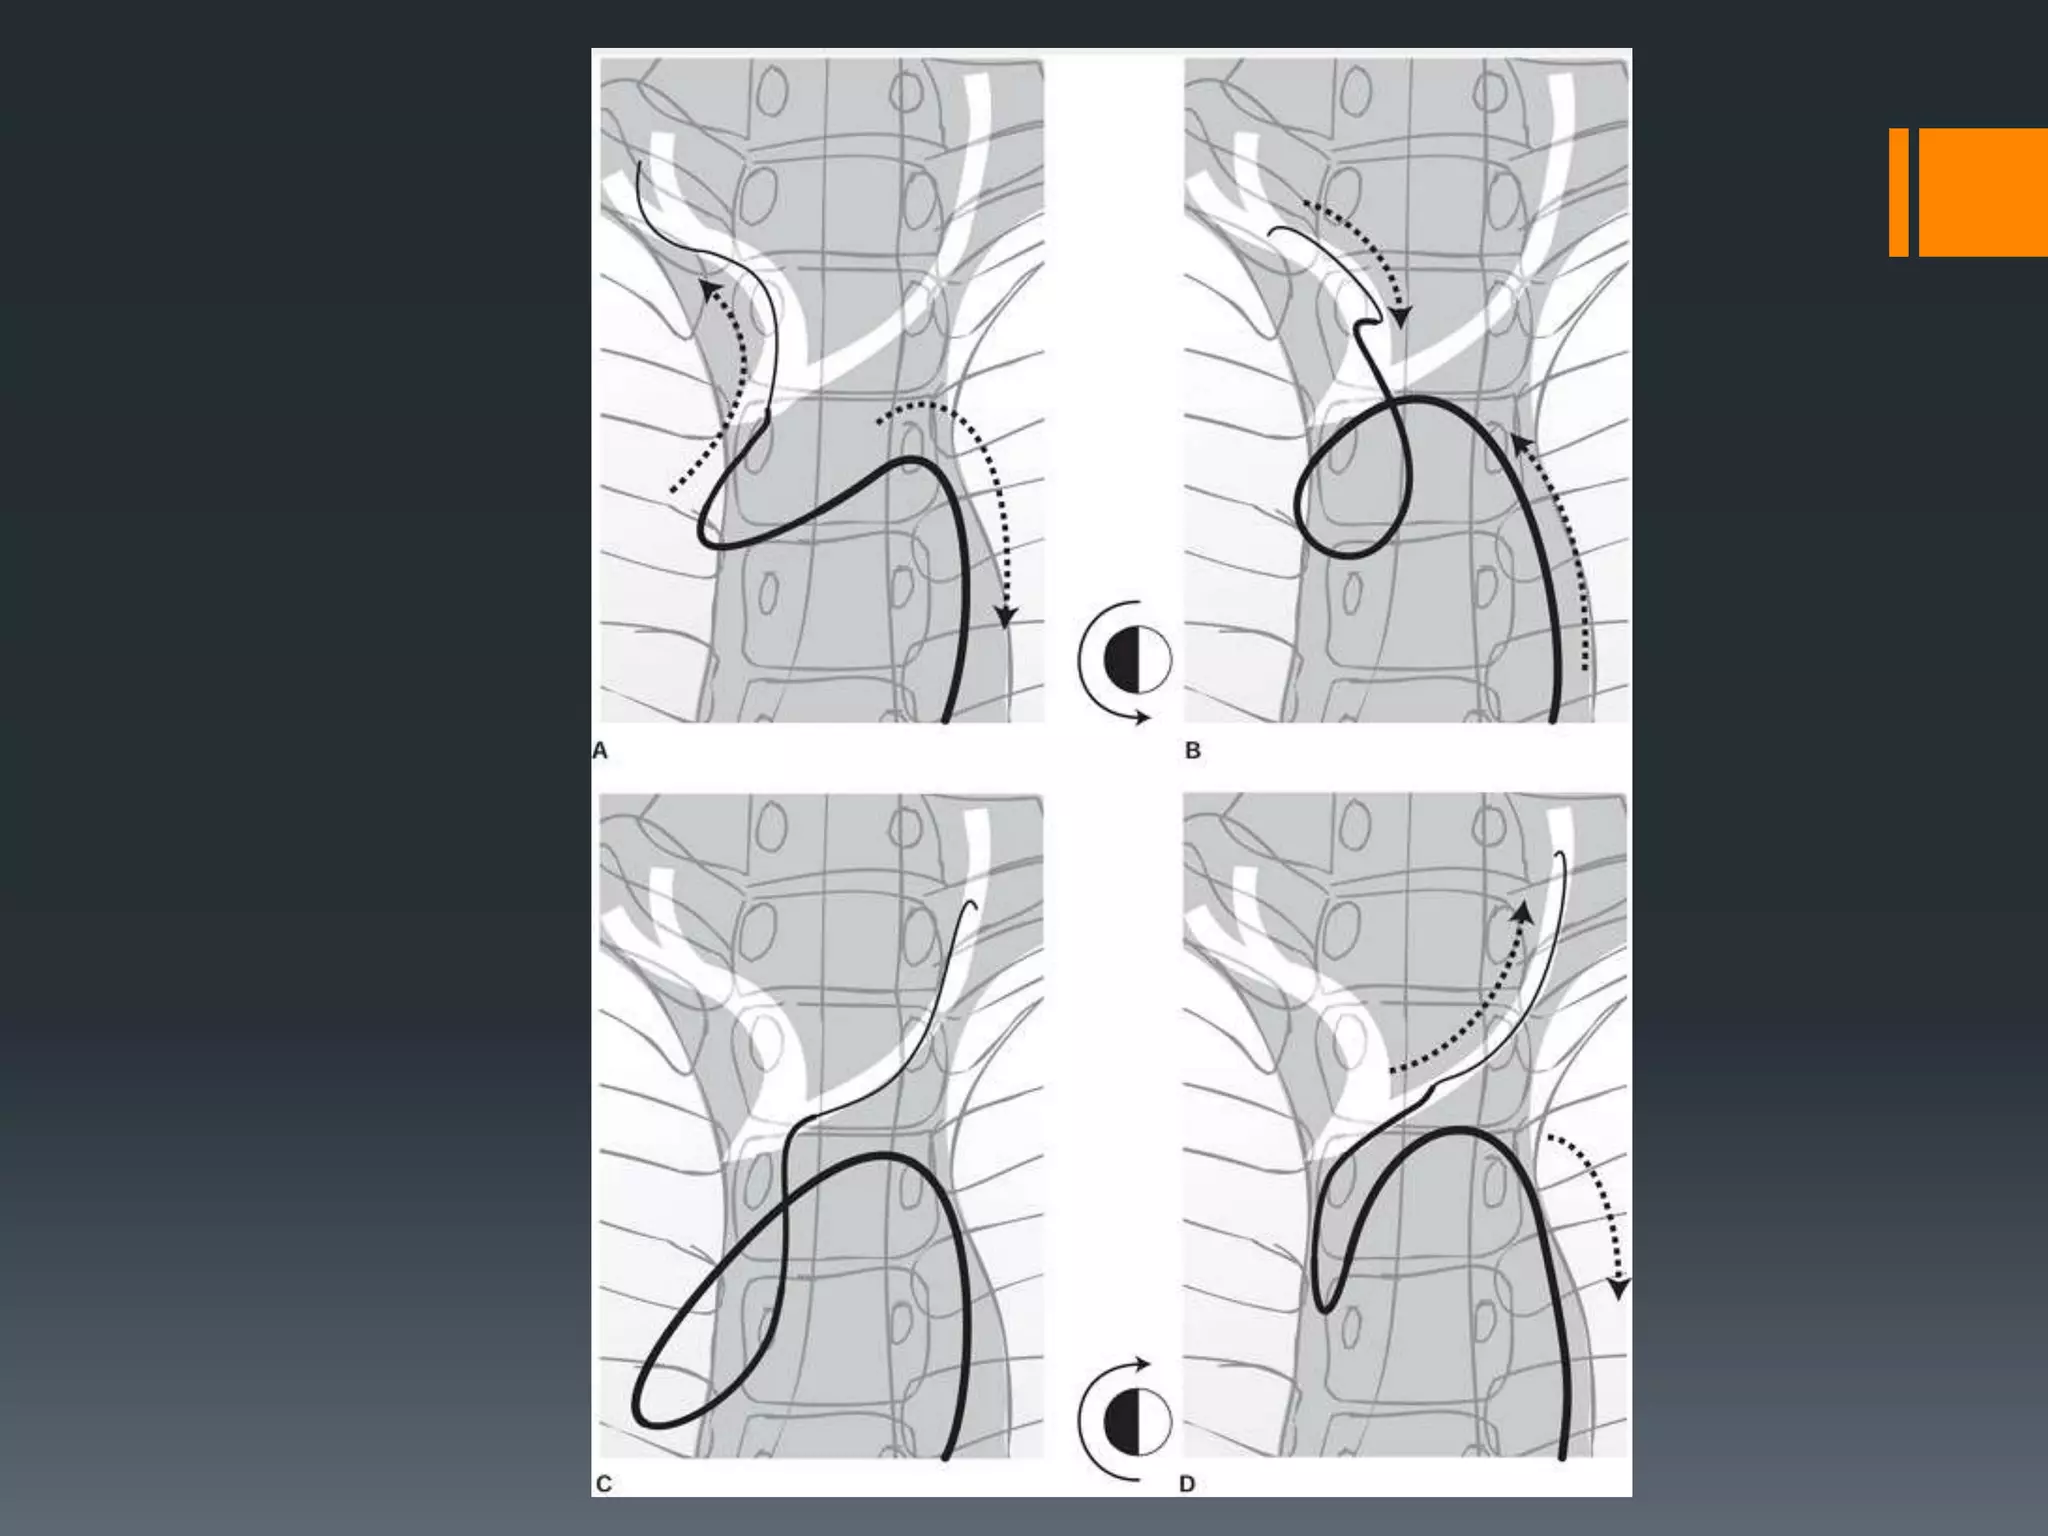

This document discusses tricks and techniques for difficult cannulations during neurointerventional procedures. It outlines strategies for accessing the aortic arch, internal carotid artery (ICA), and areas distal to aneurysms. Long sheaths, distal access catheters, and co-axial techniques are presented as options that have improved cannulation success. Guidance on sheath and catheter selection is provided for different vessel paths. The importance of catheter placement as high as possible in the ICA is emphasized. Reverse curve cannulations are also mentioned. Overall, the document stresses that careful cannulation is critical for procedural success and different strategies may be needed depending on the vessel target.